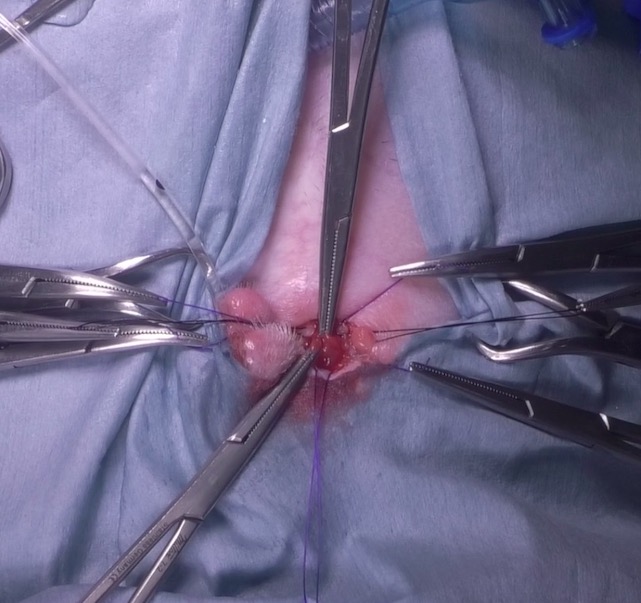

腹壁と膀胱を縫い合わせている写真です。

糸で膀胱と腹壁を固定します。これは、膀胱内容物が腹腔へ漏れないようにするためと、膀胱内の結石をとる作業中に膀胱が腹腔内に戻ってしまうのを防ぐために行います。

ここまでくるといおいよ膀胱を切開します。メスで膀胱切開を行い、膀胱内に腹腔鏡カメラを挿入します。